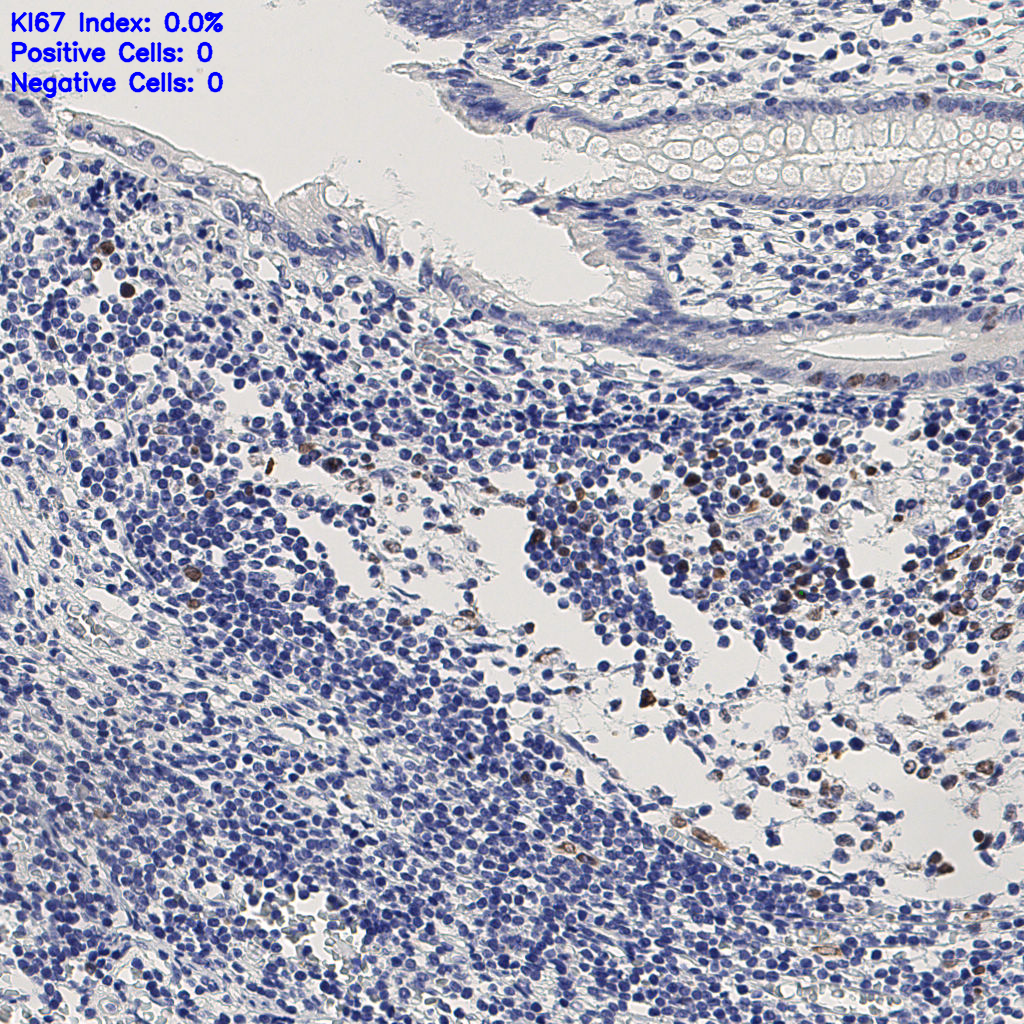

7.85%

Ki67 指数

阴 1104 阳 94

slice_9_20_x8064_y17920.png

slice_9_20_x8064_...